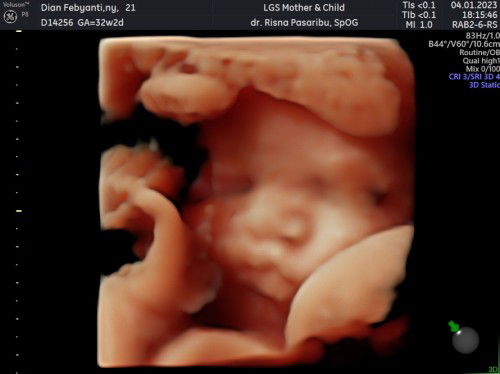

Hpl 28feb lahir anak pertama 21feb masyaAllah🙏

MasyaAllah alhamdulilah telah lahir anak pertama saya di 39minggu hpl28feb lahirnya tgl 21feb jam 21.25 bb 2,7 jk perempuann lahir normal perjuangan pecah ketuban dluan masih pembukaan 1 dan ketuban udh mau abis blm ada mules cuma di infus ditunggu pembukaan nambah klo ga nambah lngsung dirujuk tapi alhamdulilah pembukaan nmbah bbrpa jam dengan cepat beda dengan perkiraan bidan dan mules bner” ga terlalu berasa, kerasa” di pembukaan 8 kuasa allah selalu ngamalin doa diperlancar lahiran dan makan kurma ditambah solat tahajud pas mau dkat hpl semuanya dipermudah masyaAllah🤲🏻 semoga bunda” yg udh dket hpl ddnya belum lounching di segerakan juga yaa🤗 #firstmom #firstbaby